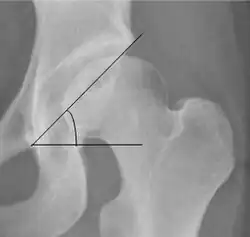

| Tönnis angle |

Slope of the sourcil (the sclerotic weight-bearing portion of the acetabulum) | 0 to 10°

| Caput-sourcil angle[12] |

Superior to the Tönnis angle in cases without joint space narrowing or subluxation.[12] The medial point of the sourcil is defined as being at the same height as the most superior point of caput femoris. | −6 to 12°[12]